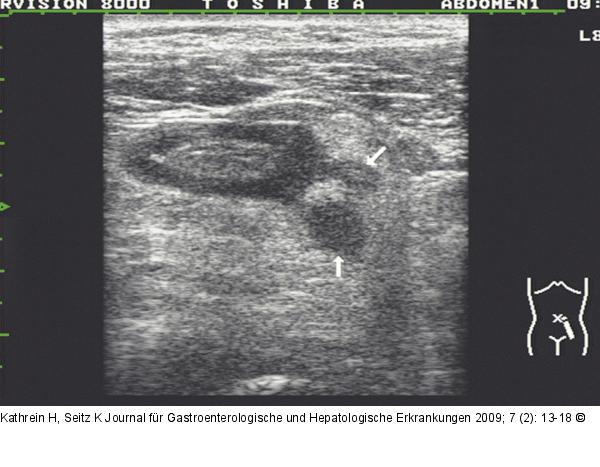

Abbildung 3: Divertikulitis - Peridivertikulitis Divertikulitis/Peridivertikulitis: 2 Divertikel mit echoarmem Inhalt, möglicherweise beginnende Abszessbildung (Pfeile); die Umgebung der Divertikel auffallend echogen dargestellt (entzündliche Weichteilreaktion). |

Divertikulitis/Peridivertikulitis: 2 Divertikel mit echoarmem Inhalt, möglicherweise beginnende Abszessbildung (Pfeile); die Umgebung der Divertikel auffallend echogen dargestellt (entzündliche Weichteilreaktion). |